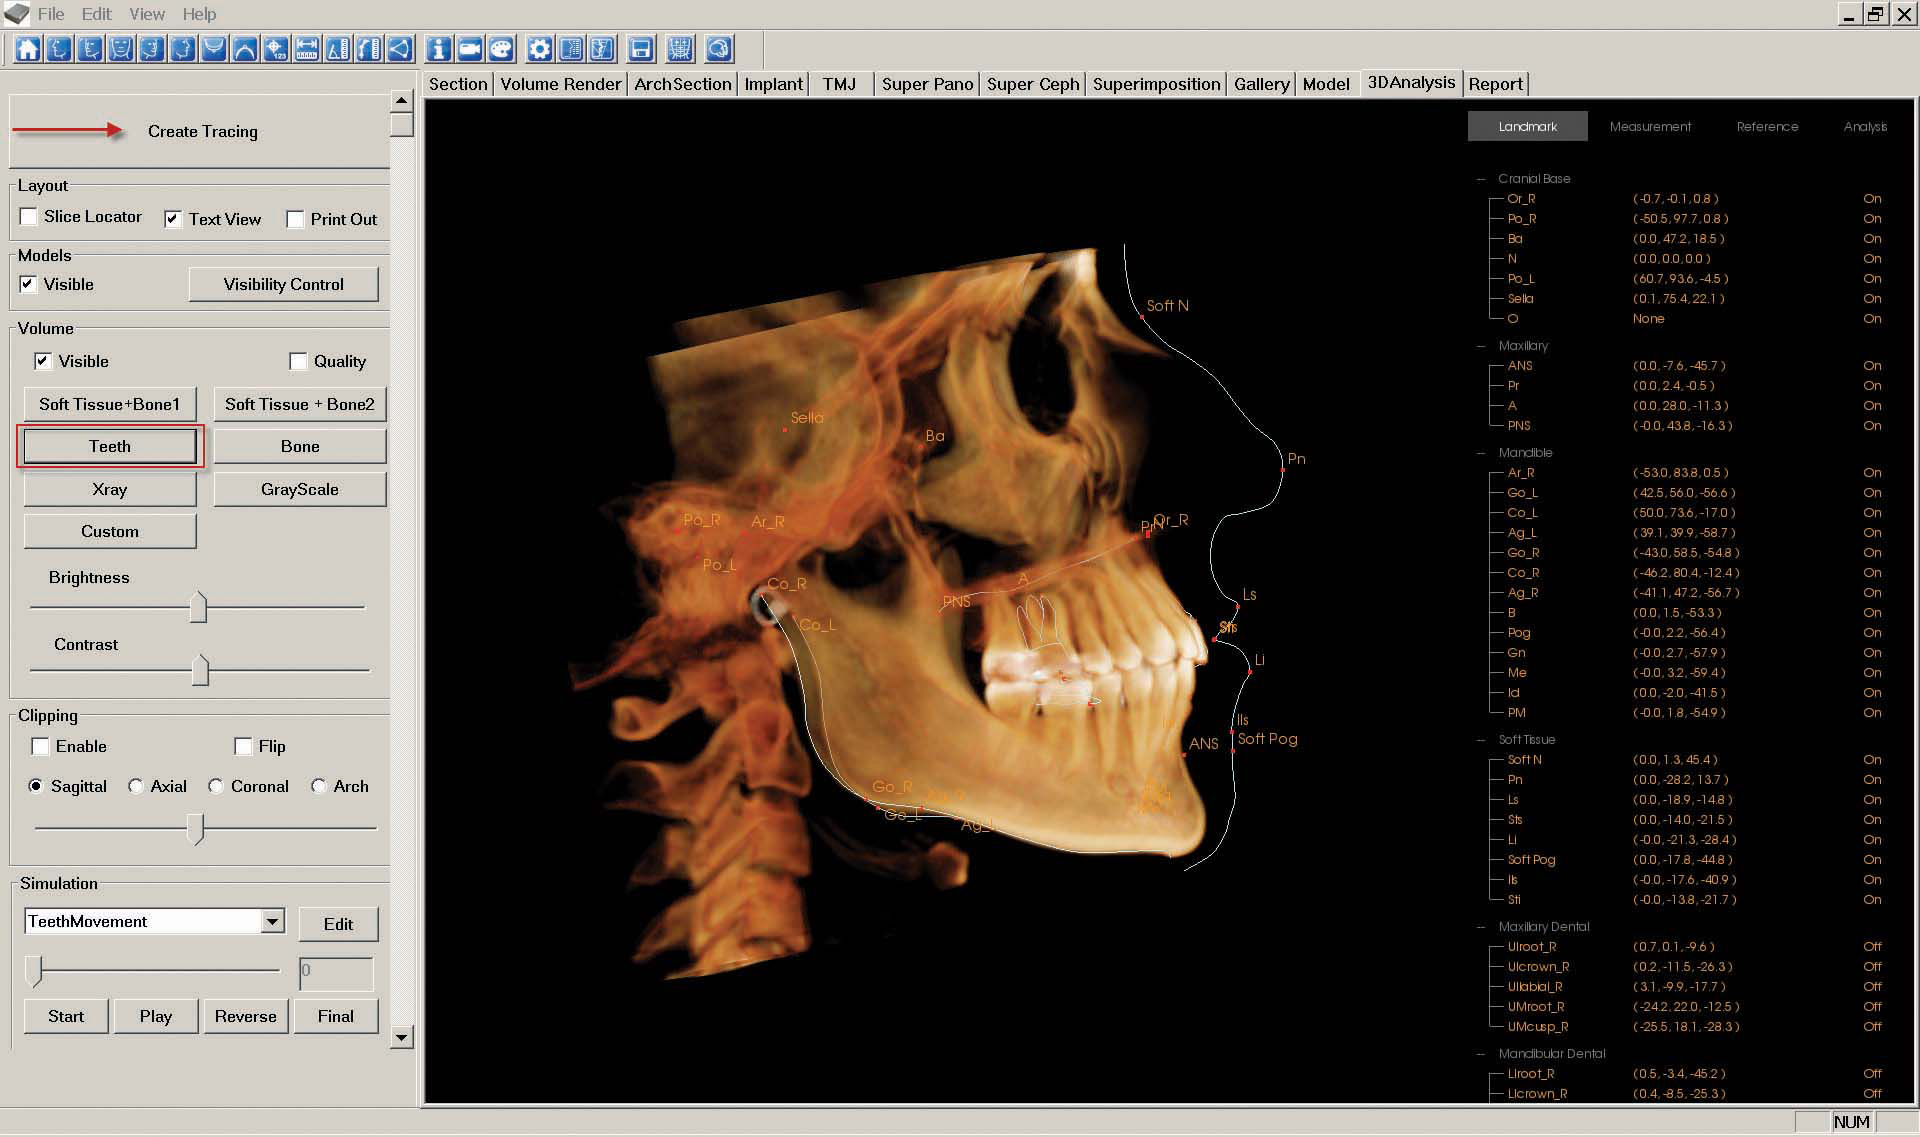

i. The "Lateral Ceph Tracing" is created in the "3D Analysis" tab. First, click the "Right view" icon at the top of the screen, then click "Create Tracing" and follow the prompts to trace the ceph to your doctor's preference. Then you might want to select the "Teeth" view.

As described in step 7, "Capture to Gallery" in whole view and name the image "Lateral Ceph Tracing."